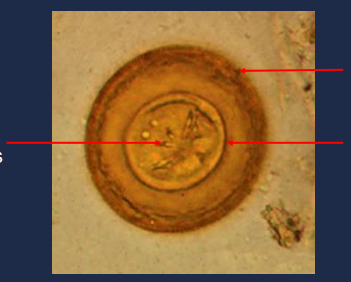

Diphyllobothriid eggs, operculum

____________________ in an unstained wet mount of stool. What do you call the part that is open?

13

New cards

Diphyllobothriid egg

____________________ in an unstained wet mount of stool.

14

operculum

State the name of the part on the upper portion of the picture.

15

immature embryo

State the name of the part of middle portion of the picture.

16